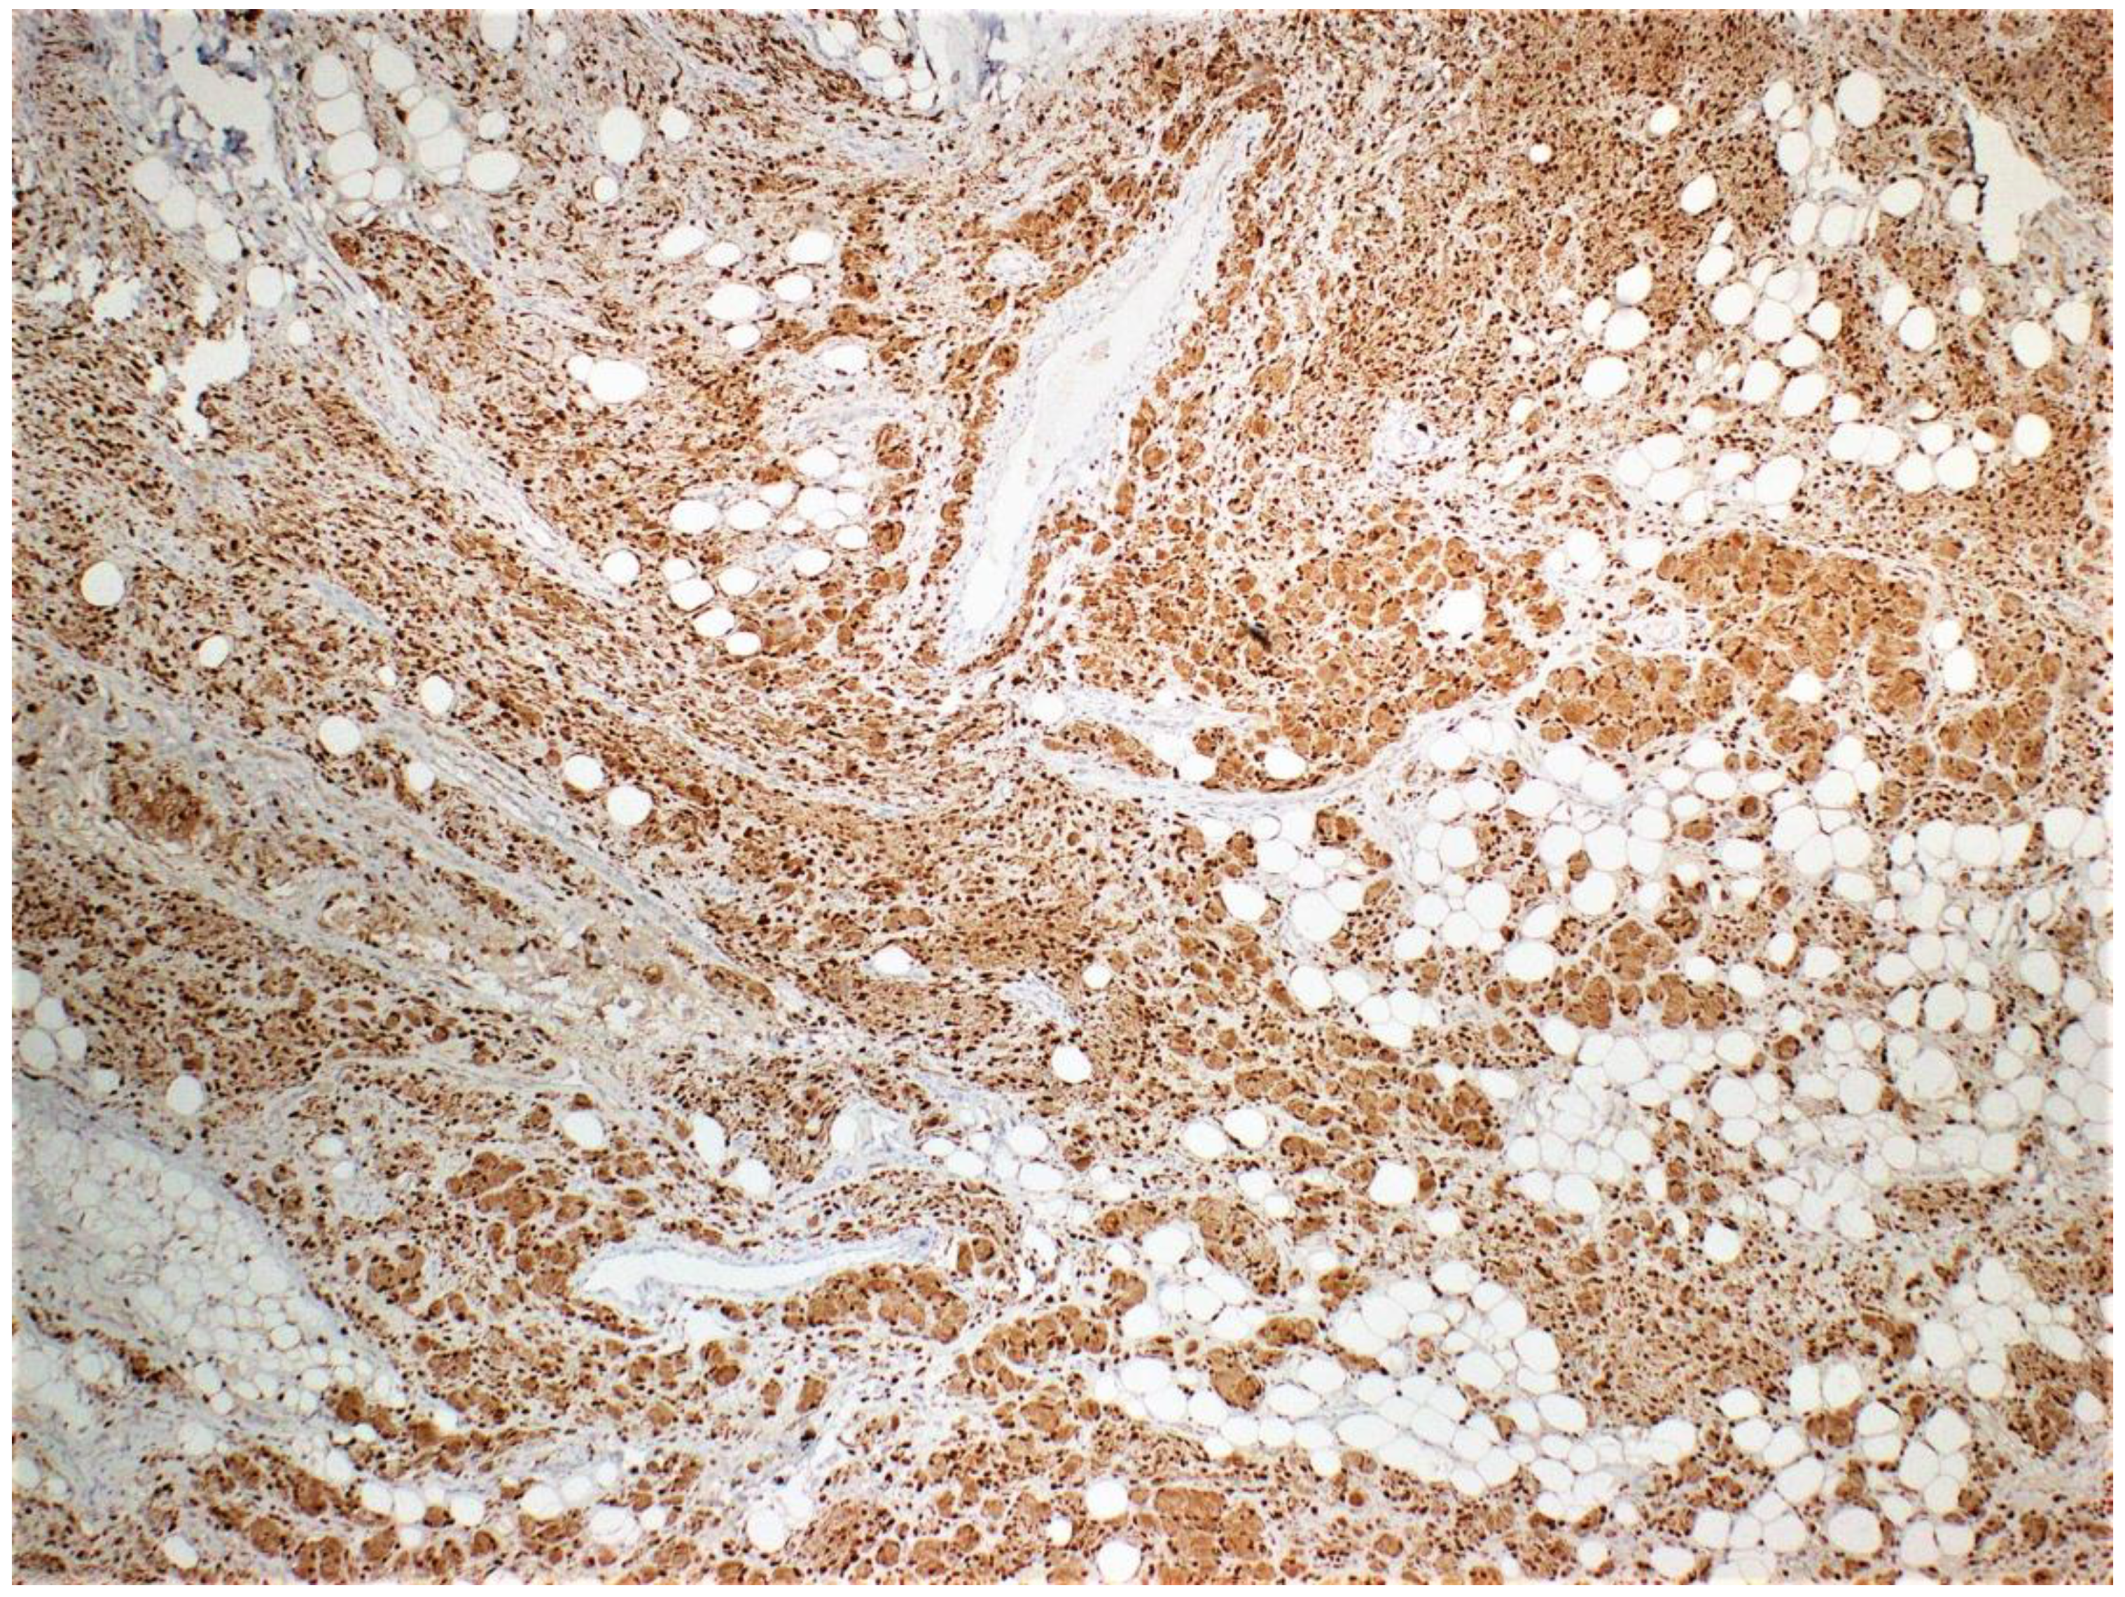

Due to the atypical presentation, gross examination, and microscopic examination, immunohistochemistry stains were ordered to characterize the lesion. The results were positive for HMB45, S100 (Figure 4), CD34 (Figure 5), and Melanin A and negative for neurofilament.

Plexiform neurofibromas have varying presentations depending on the extension depth and location site. They arise from deeply located spinal nerve roots and have a highly ill-defined hyperpigmented and torturous appearance. Common symptoms include pain, numbness, and mass effect. Similar to diffuse neurofibroma, they can grow immensely, often surrounding multiple nerve fascicles [1,4]. The subtype is found in approximately 30-40 % of patients with NF1 and is considered pathognomonic for the hereditary disorder [1,4]. Diffuse neurofibroma is differentiated from plexiform neurofibroma subtypes by its defining characteristic of dermal and subcutaneous proliferation that irregularly entraps adnexa structures (Figure 3) and invades underlying adipose tissue (Figure 1 and Figure 2). Pseudomeissenerian bodies (Wagner-Meissner bodies), composed of eosinophilic fibrillary and whorled Schwann cells, are a unique characteristic feature of diffuse neurofibroma [1,10]. S100 is a sensitive but nonspecific marker for Schwann cells in neurofibromas (Figure 4). In diffuse neurofibromas, CD34 staining is fingerprint-like (Figure 5) because it stains admixed spindled fibroblasts in between collagen bundles [1]. Plexiform neurofibroma can be differentiated from diffuse neurofibroma due to its serpentine growth pattern, possible atypia, and irregular hypertrophic nerve fascicles [1,4]. The patient’s clinical presentation of headache and tenderness is more in line with a plexiform neurofibroma. However, histopathological findings were consistent with a diffuse neurofibroma as microscopic examination did not reveal nuclear atypia or hypertrophic nerve fascicles. Additionally, she did not exhibit the usual alternative traits associated with NF1. The neurofibroma subtypes are microscopically similar because they comprise loosely arranged ovoid to spindle cells with hyperchromatic buckled to wavy nuclei within a background of myoxid to pale pink collagenous matrix [1,8,9].

Figure 4. S100 staining is diffuse and strongly positive.